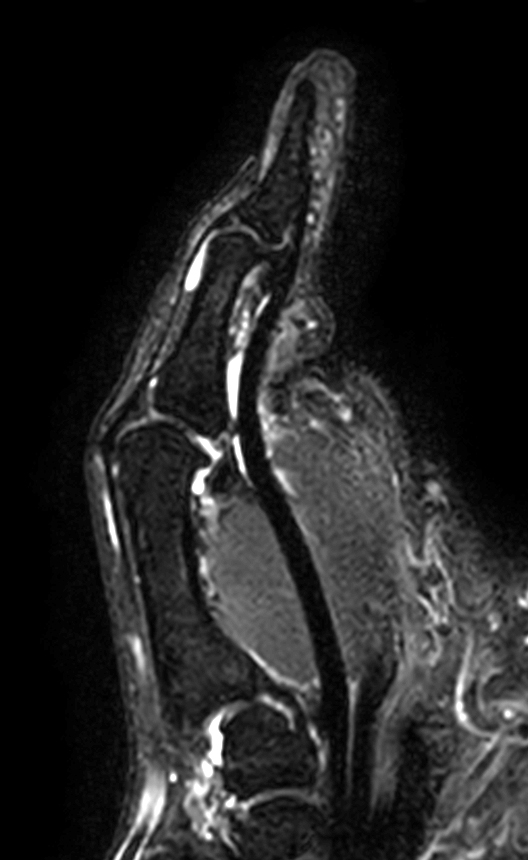

Patient with pathology on the thumb. ExamCard includes mDIXON XD TSE to achieve uniform, complete and consistent fat-free imaging. It simplifies the scan procedure by providing multiple image types in one single scan, including with/without fat suppression contrasts.

T2w TSE mDIXON XD (In Phase)